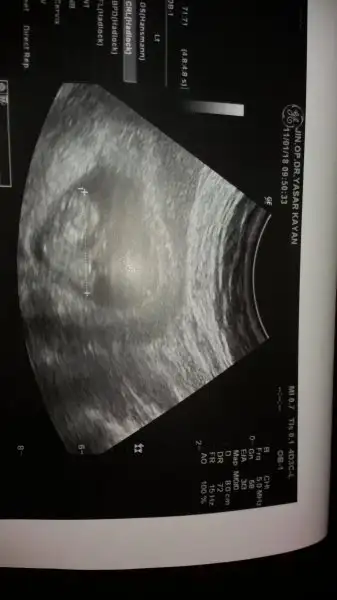

Senle satımız aynı, maşallah bebişine, darısı başıma inşallahKızlar doktordan geliyoruz bi mahşallahınız alırız:) sata göre 6+4tük 6+5çıktık ölçümlerde. Kalp atışlarımızı duyduk suyumuz kan akışımız herşey yolundaymış. Bulantı içinde premesis plus diye bi ilaç verdi doktorum. Bitkiselmiş içinde zencefil kökü ve b vitaminleri varmış. Bulantını tamamen kesmez ama hafifletir dedi. Ayrıca bulantılarının olması çok iyi bişey dedi bu bebeğinin geliştiğini ve iyi olduğunu gösterir dedi. :)